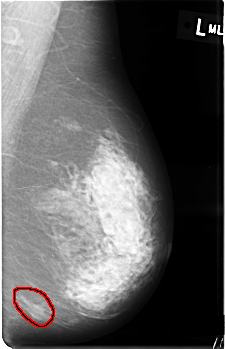

C_0362_1.LEFT_MLO

LEFT_MLO LINES 4528 PIXELS_PER_LINE 2920 BITS_PER_PIXEL 12 RESOLUTION 50 OVERLAY

FILE: C_0362_1.LEFT_MLO.OVERLAY

TOTAL_ABNORMALITIES 1

ABNORMALITY 1

LESION_TYPE MASS SHAPE OVAL MARGINS ILL_DEFINED

ASSESSMENT 4

SUBTLETY 5

PATHOLOGY BENIGN

TOTAL_OUTLINES 2

BOUNDARY